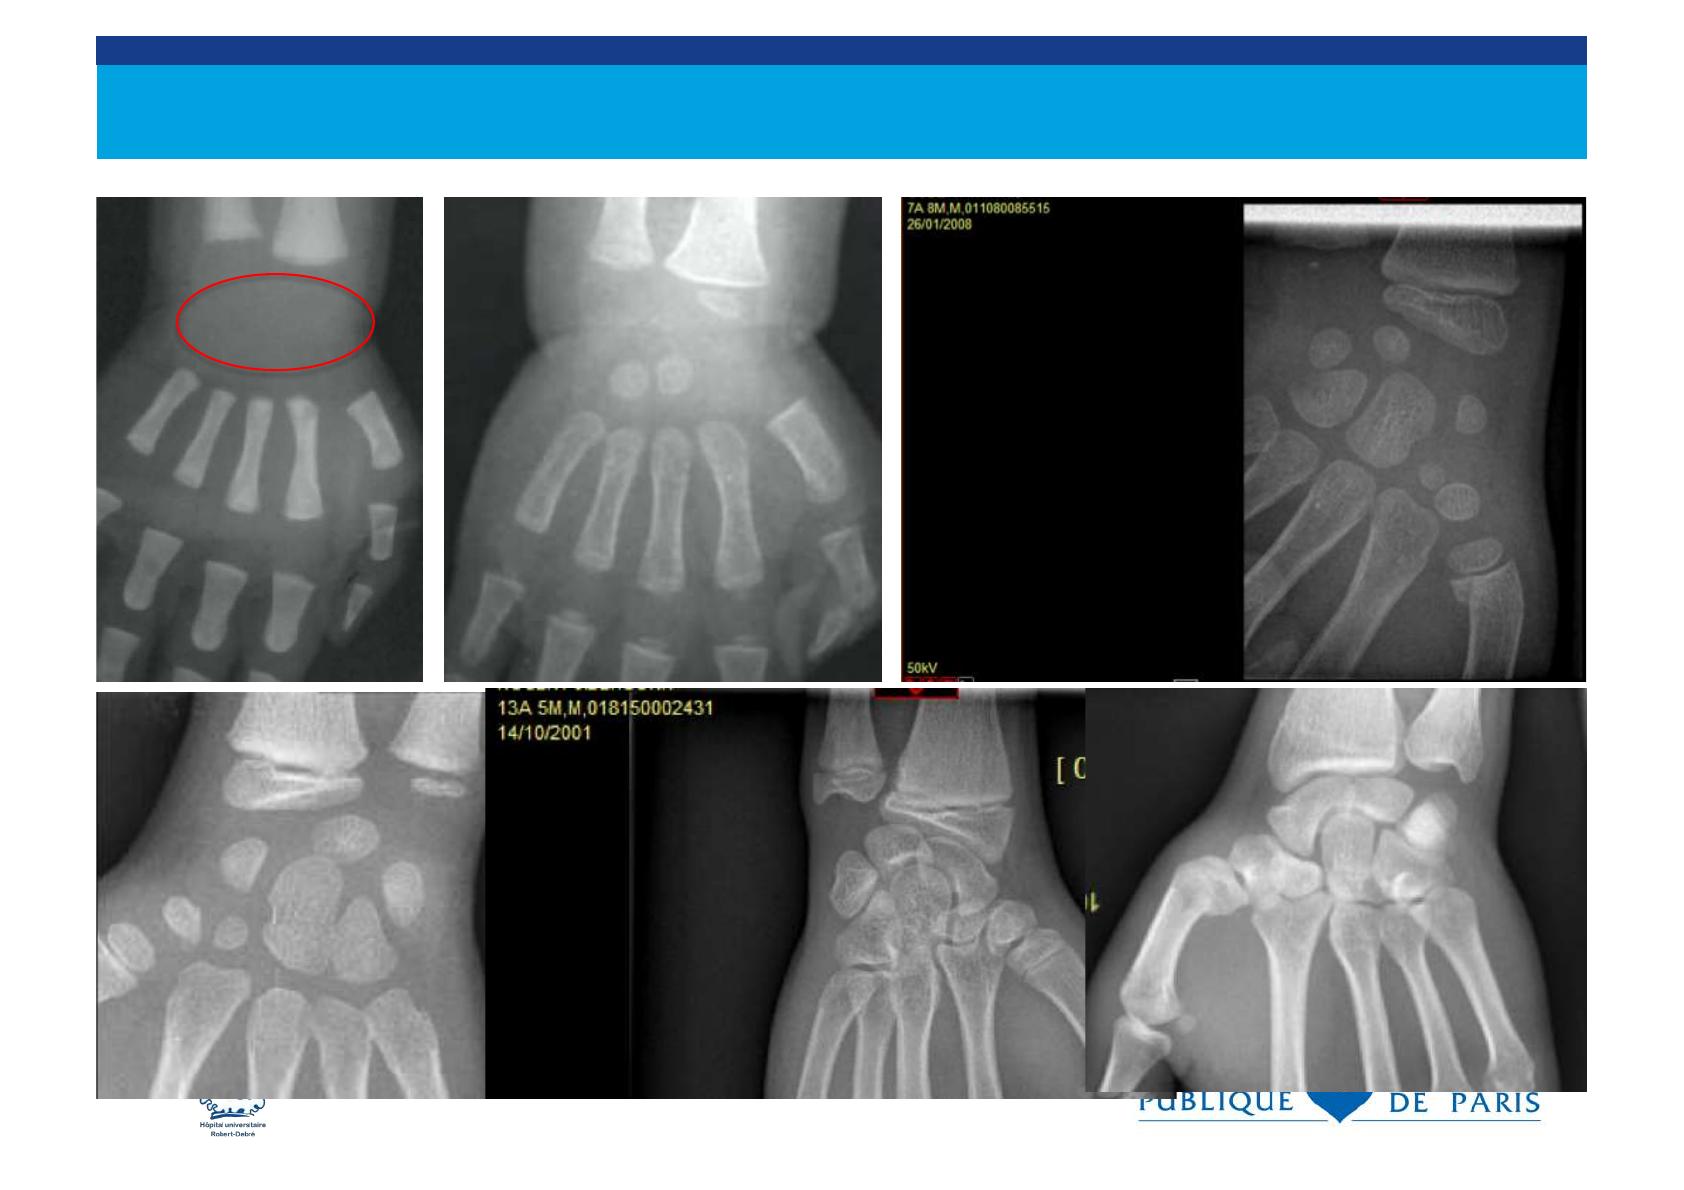

Le cartilage de croissance

. sépare l’ épiphyse de la métaphyse et il est

radiotransparent

. fragile et vulnérable aux traumatismes

. les fractures peuvent traverser le cartilage de

croissance.

. Les traumatismes du cartilage de croissance

déterminent le pronostic des fractures de l’ enfant

métaphyse

épiphyse

cartilage de croissance